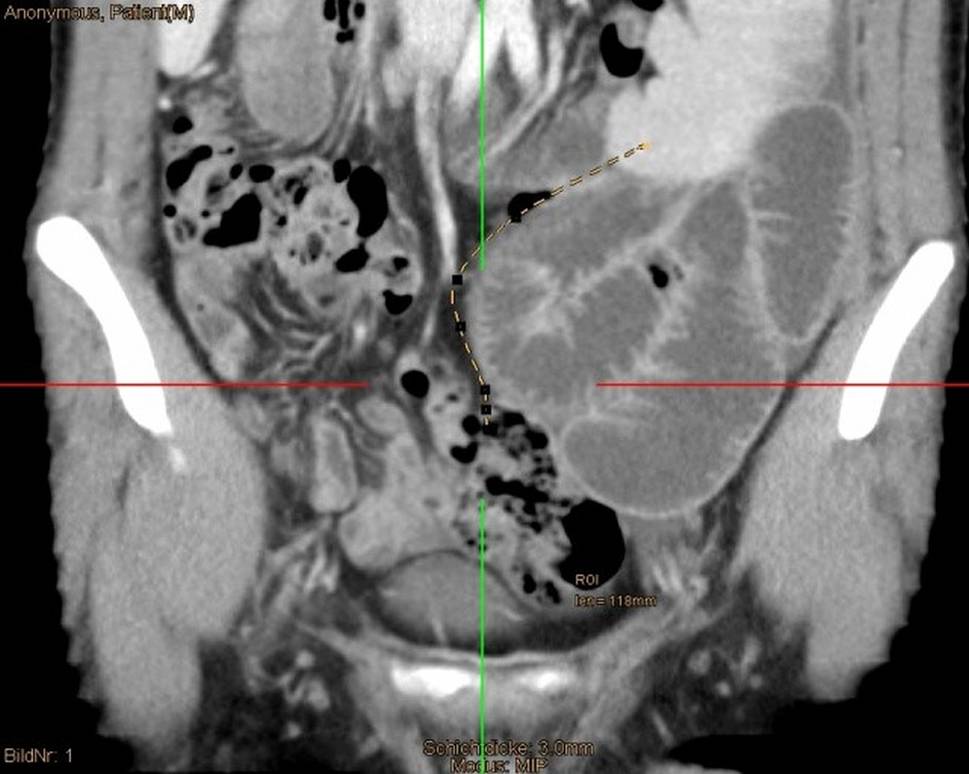

Fig. 2

Maximum intensity projection (MIP) from a venous CT scan with the appendix’s planning path (dashed yellow line) from the medial caecum to the distal spleen. Dilated small intestine bowel loops can be detected in the left lower abdomen